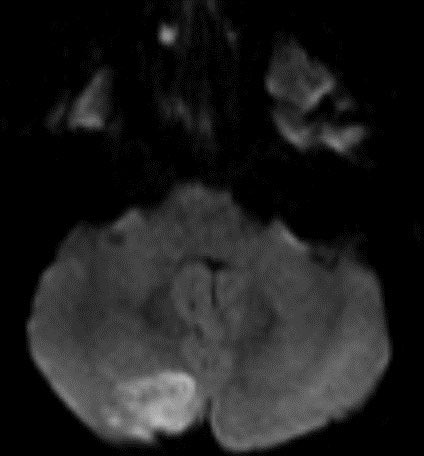

Typically there is no to little enhancement and high signal on DWI due to T2 shine-through w/ high signal on ADC x.com

💡 Both Lhermitte-Duclos & Medulloblastoma SHH can have a striated appearance! Use DWI/ADC, density on CT, & enhancement to distinguish!

💡 Hypercellular tumor so DENSE on CT and DIFFUSION RESTRICTION (consistent feature)